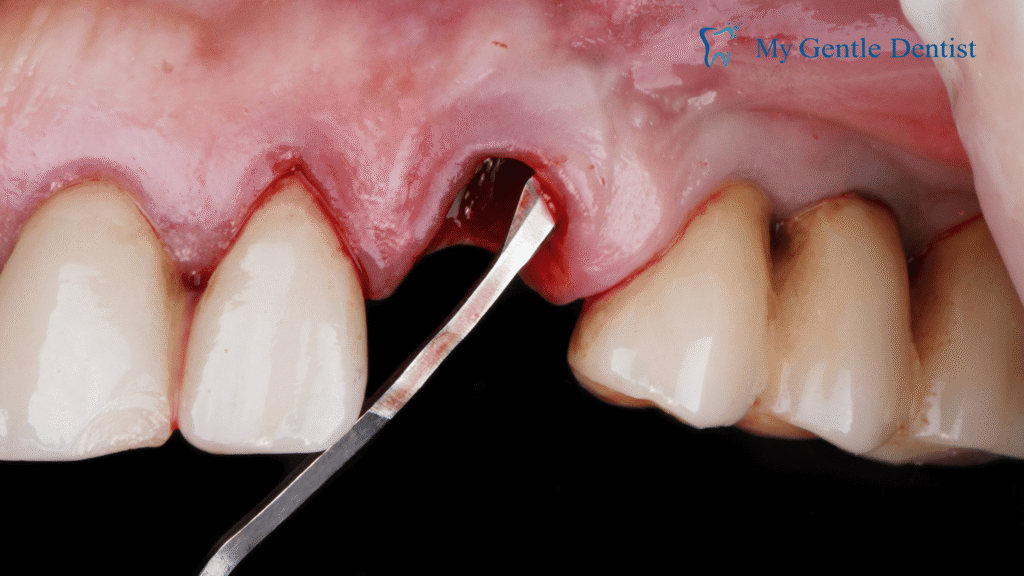

If gum disease has progressed beyond its early stages, you may develop deep pockets between your gums and teeth. These pockets create spaces where bacteria can thrive, leading to infection and potential bone loss. Pocket reduction surgery, also known as flap surgery, is a surgical procedure designed to clean out these pockets and prevent further damage.

How Pocket Reduction Surgery Works

During this procedure, the periodontist folds back the gums to remove bacteria, plaque, and infected tissue from the deep pockets. Once the area is cleaned, the gums are sutured back in place, reducing the size of the pockets and making it easier to maintain oral hygiene.